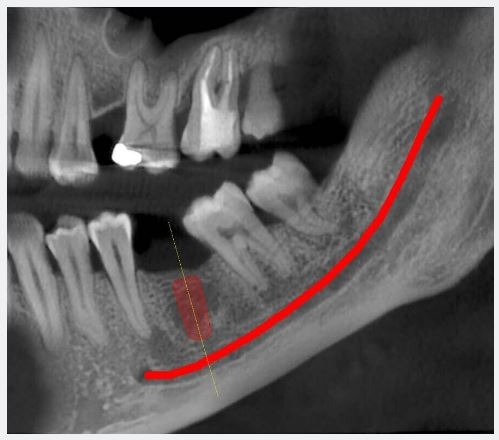

Sezioni Tomografiche (TC/Tac) e Ricostruzioni 3D dei mascellari Ortopantomografia delle arcate dentarie a bassa emissione di radiazioni X Ortopantomografia delle arcate specifica per uso pediatrico Rx Stratigrafia dei condili mandibolari compresa ATM Emimandibola dx/sx Adatta per adulti e bambini, veloce e indolore, consente di ottenere in tempo reale i referti necessari per le diagnosi e la pianificazione delle cure. Lo specialista garantisce le stesse tariffe applicate presso le strutture sanitarie specializzate esterne pur offrendo un prodotto avanzato, confortevole e sicuro.